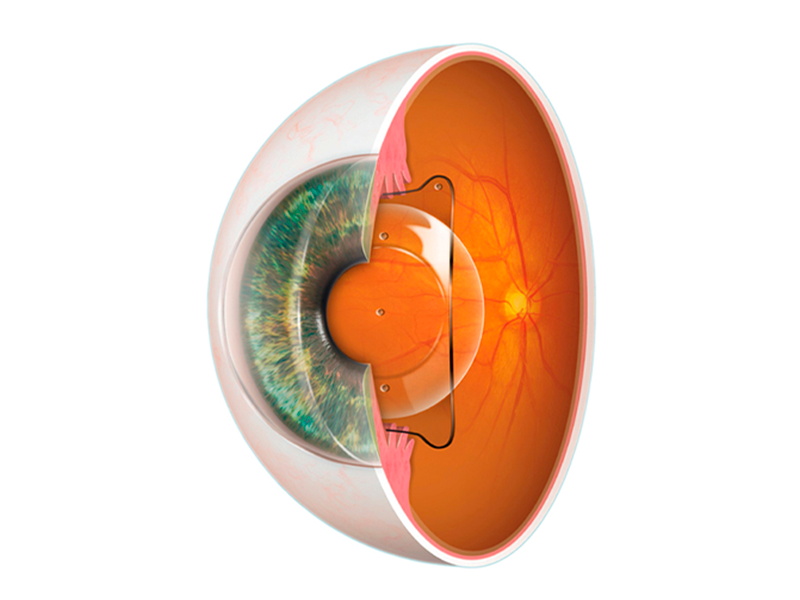

تحسين الرؤية لمسافة واحدة مع استقرار وأمان تام بعد العملية.

رؤية واضحة للمسافات القريبة والمتوسطة والبعيدة، وتقليل الحاجة للنظارات بعد العملية.